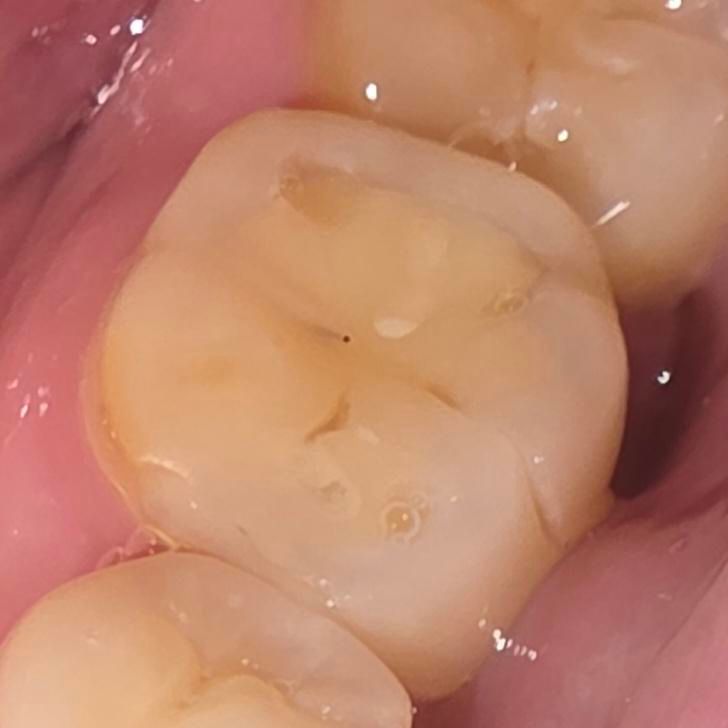

레진했던부위인데 우측에 보면 금이 많이 갔고 씹을때마다 아파요. 해외인데 보험을 못들어서 병원비가 너무 비쌀거라 도무지 갈 엄두가 안나는데요.. 외관상 이거 어찌해야할까요? 인레이도 어렵고 그냥 임플란트로 가야하는건가요? 아니면 다른대책이 있을까요,

저상태에서 일반 보철치료 건너뛰고 임플란트로 가야할 근거가 없습니다 엑스레이 사진도 있다면 도움이 될 것 같은데 일단은 빼야할 근거가 없네요 마모가 심한 편이니 크라운으로 갈 것 같습니다